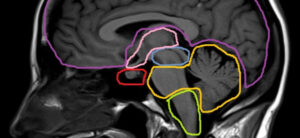

Анатомия цистерн головного мозга

Цистерны головного мозга – это полости и промежутки, расположенные внутри головного мозга и заполненные специальной жидкостью — цереброспинальной жидкостью. Важнейшей функцией цистерн является защита головного мозга от повреждений, а также обеспечение его нормальной работы. Цистерна мозжечка – находится в задней черепной ямке и заполняет промежуток между задним мозговым сосудистым протоком и верхней поверхностью мозжечка. Цистерна …